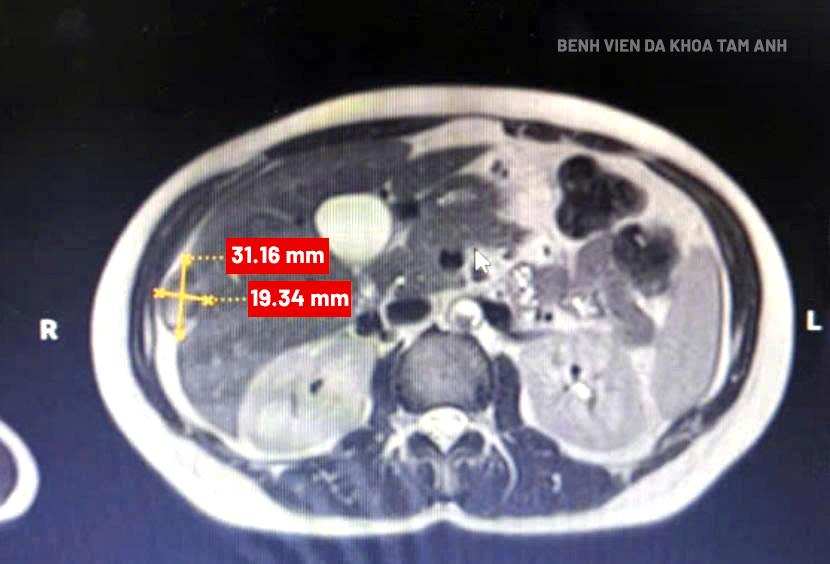

MRI image showing the fetal mass implanted in Sen's liver. *Photo: Tam Anh General Hospital*

An MRI scan at a hospital revealed a lesion under Sen's liver capsule, measuring 30x28x17 mm, which doctors initially diagnosed as a digestive disorder. The patient did not exhibit typical signs of ectopic pregnancy, such as a missed period or vaginal bleeding. Doctor Hoang My Kim, from the Obstetrics and Gynecology Center at Tam Anh General Hospital Hanoi, identified this as a case of fetal implantation within the liver capsule. Fetal implantation in the liver capsule occurs in 1/15,000 pregnancies. If not detected early, the developing fetus can cause the liver capsule to rupture, leading to massive blood loss and a high risk of death.